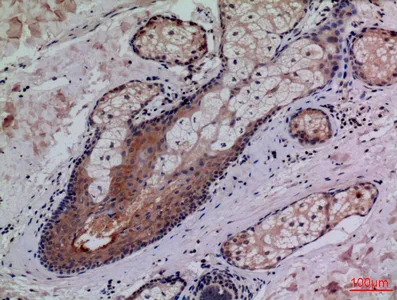

CD68 Rabbit Polyclonal Antibody

Cat: APRab08436

Size1:50μl Price1:$118

Size2:100μl Price2:$220

Size3:500μl Price3:$980